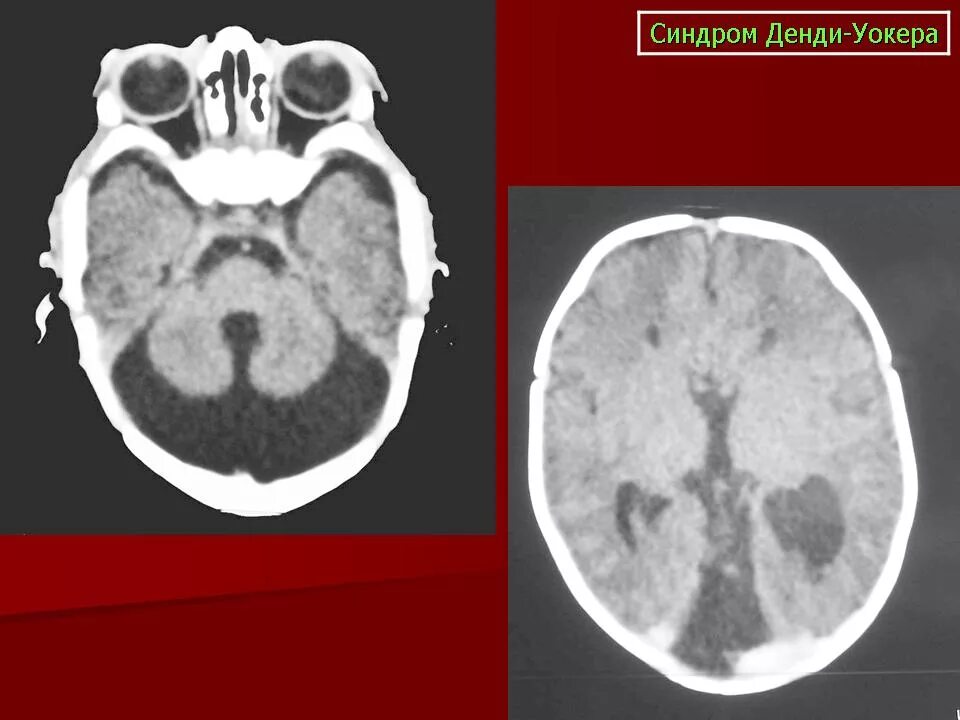

Денди уокера мрт